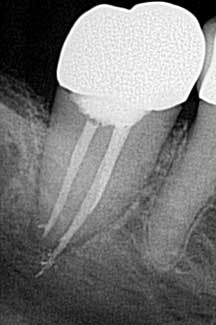

• Access perforations

Drill, poke around. Drill some more. Hmm. I’ve got to be getting close. Let’s just take an x-ray to see how close we are . . . oops! Yeah, that’s happened to me and it’s not how I like to start my root canals (figure 1). The cause of perforations during access is primarily due to lack of attention to the degree of axial inclination and failure to hold the bur parallel to the tooth. (1) Inadequate access can also lead to misdirection and unintended gouging. Signs of perforation include sudden pain, hemorrhaging, burning pain or bad taste during irrigation, periodontal ligament reading from the apex locator, and a radiographically malpositioned file. (1) Prevention includes understanding tooth morphology, accessing without a rubber dam (in instances where angulation, calcified chambers, and misoriented crowns skew tooth alignment), (1) having multiple radiographs to reference, and patience . . . lots and lots of patience, especially when you have small, calcified chambers that want to be eluded.